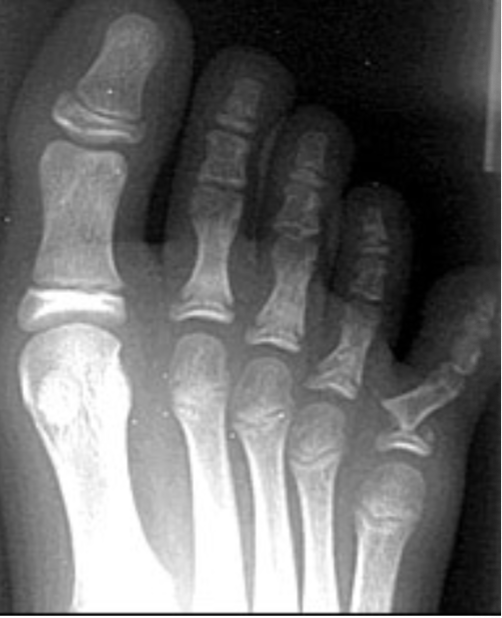

Avulsion Fracture

Occur at site of muscle, tendon, or ligament attachment; from abrupt pull, piece of bone is avulsed with soft tissue